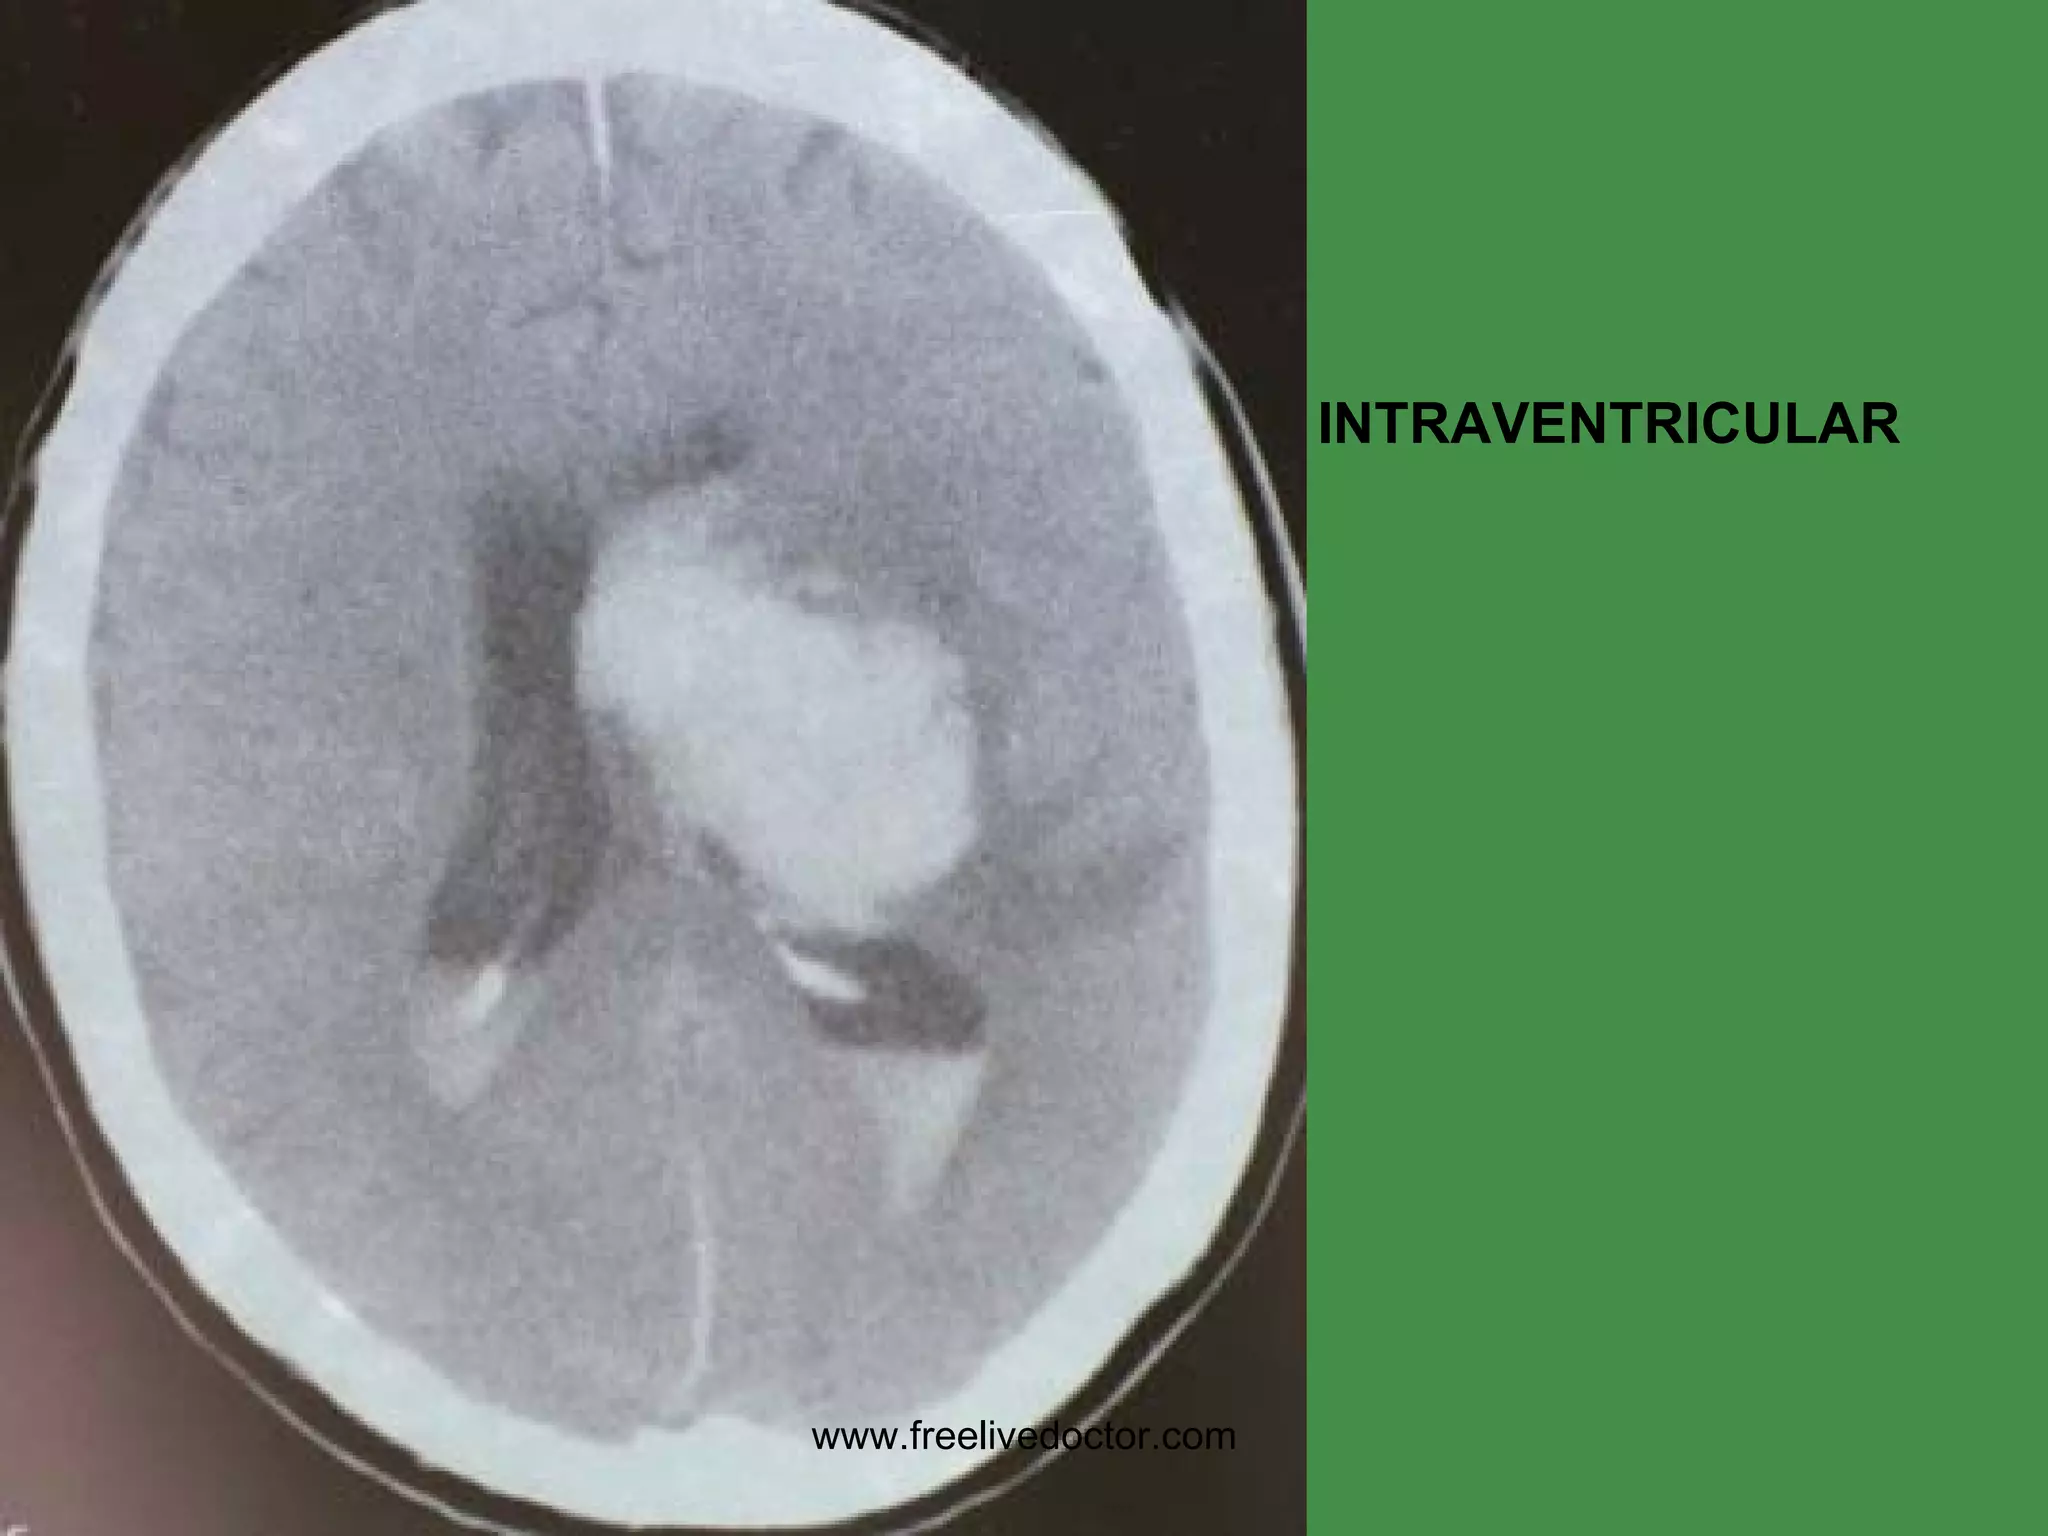

HEMATOMAS/HEMORRHAGE EPIDURAL (fx) SUBDURAL (trauma NO fx) SUBARACHNOID (arterial, no trauma) INTRAPARENCHYMAL (any) INTRAVENTRICULAR (no trauma, rare in adults, common in premies) www.freelivedoctor.com

INTRAVENTRICULAR www.freelivedoctor.com